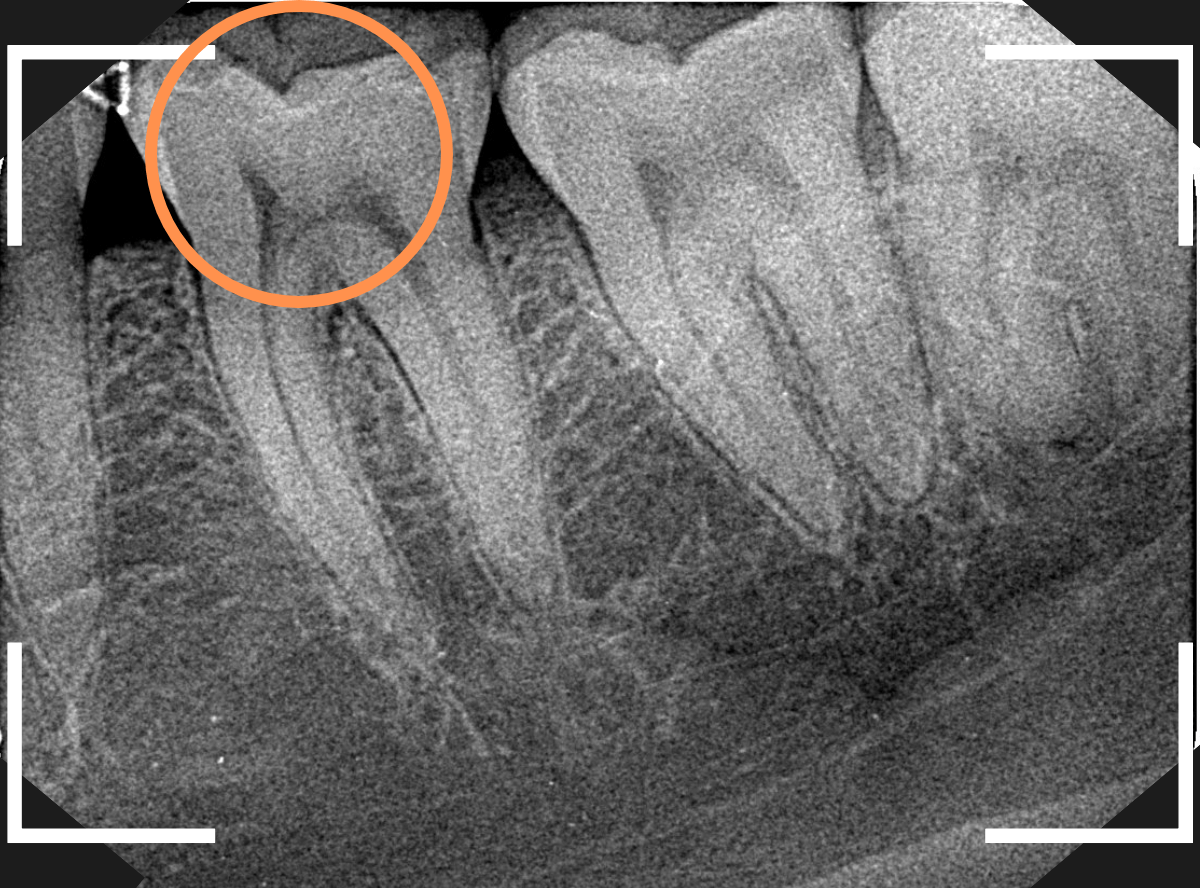

レントゲン写真で歯を確認します。

特に中に異常はなさそうですが、油断はできません。

このように大きな力がかかった歯にはレントゲンや見えない傷がついてたりする事もあります。

すると、不定期にしみや不快感が起こる事もあり、原因がわからず途方に暮れてしまう事もあるのです。